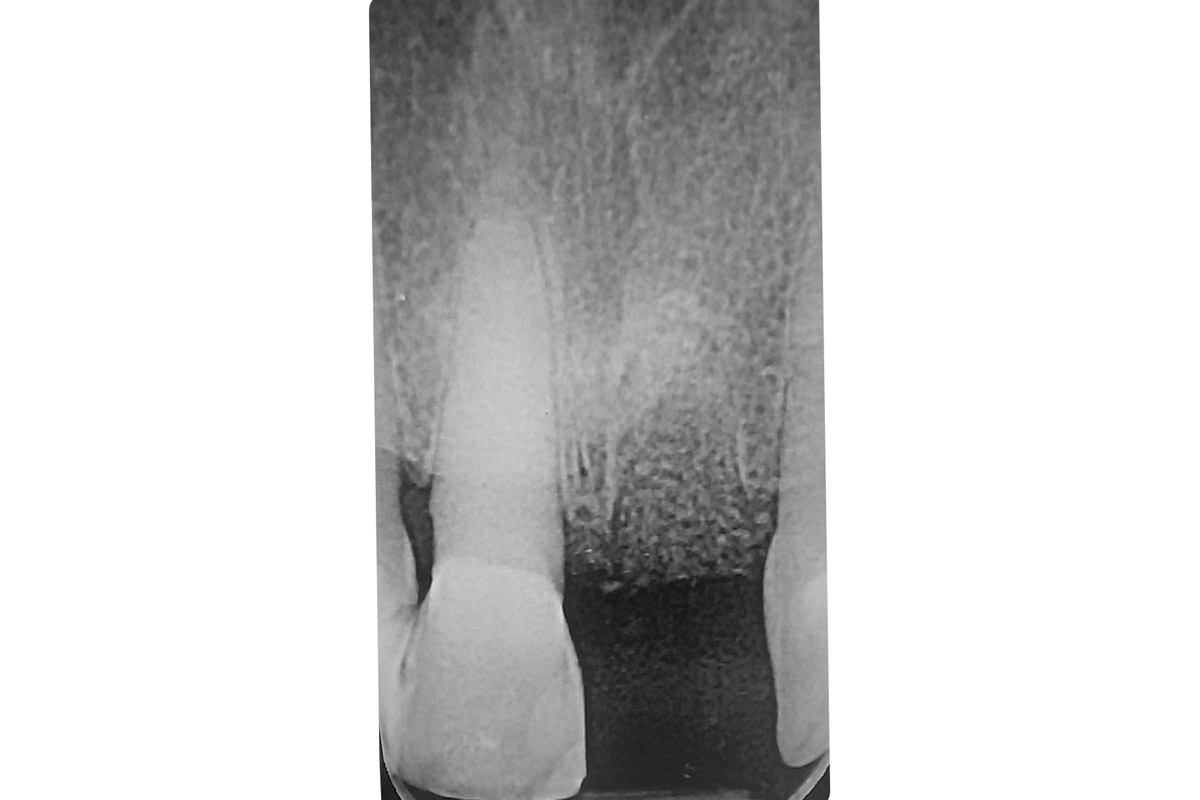

3/18 - Enoral periapical X-ray showing poor root dimensionTooth extraction and socket sealing with mucoderm® - Dr. A. Rossi